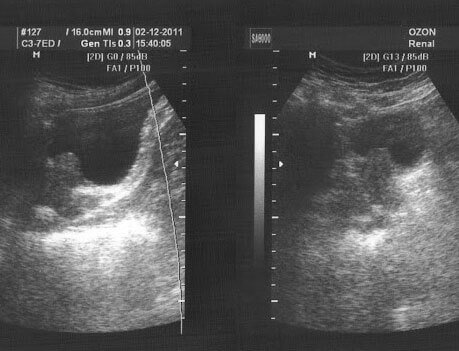

Masaža prostate je direktno djelovanje prstima na prostatu koje osigurava odljev sekreta s ljekovitim, preventivnim ciljem ili za prikupljanje materijala za analizu. Procedura je bolna i kod muškaraca izaziva snažnu neprijatnost i praćena je osjećajem boli.